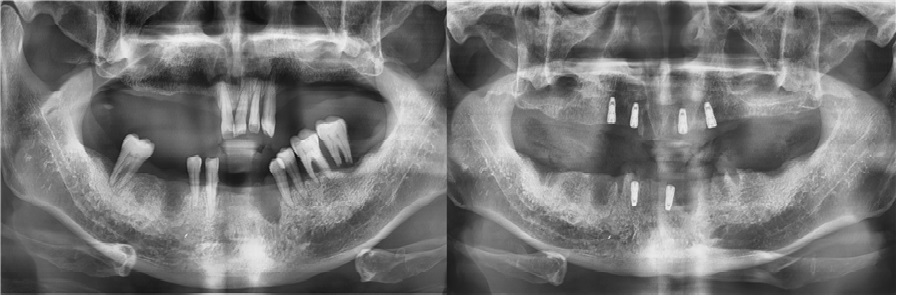

치료전후사진